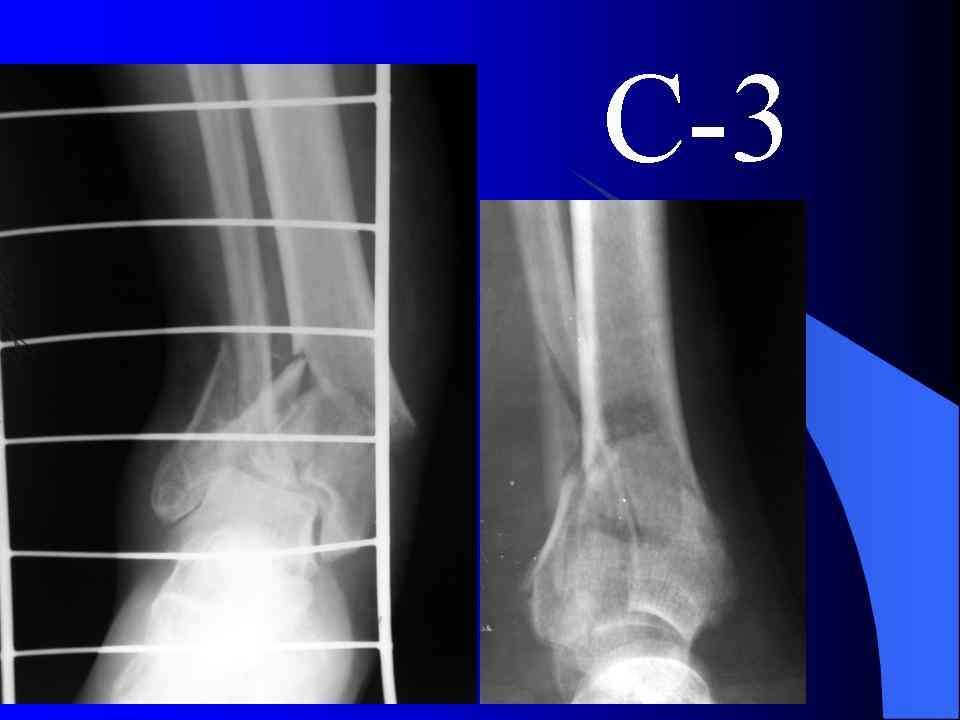

На рентгенограммах типичный перелом пилона по типу С-3. есть опыт до 100 открытых опреаций у нас в клинике. 20 примерно в год. Принцип один -все внутрисуставные переломы нуждаются в открытой репозиции и внутренней стабильной фиксации. При поступлении КТ не надо, так как получается только нагромождение костей. Истинной картины нет. Главное восстановить длину малоберцовой кости - это ключ к успеху. При поступлении меньше всего надо думать о сосудистых расстройствах, т.к. сама операция и репозиция даже сначала частичная даёт улучшение сосудитых нарушений. Причём очень быстро. Операция в 2этапа. При поступлении доступ позади наружной лодыжки, причём обязательно. После этого репозиция малоберцовой кости и фиксация пластиной 1/3 трубки под винт 3,5. Дренаж и любой аппарат наружной фиксации. Затем после спадения отёка на 5-7-10 день аппрат снимается и дугообразный разрез спереди от медиальной лодыжки 10-12 см. Главной чтобы расстояние между 1 и вторым разрезом было не меньше 7-8 см. Тогда не будет некрозов лоскутов. Таранная кость используется как матрица на неё укладываются отломки и фиксируются пицами. Ренг-контроль. Отломки лежат все отдельно, но ничего не высыпется. При переломах С-3 всегда нужна костная пластика (из крыла). Фиксация пластиной лист клевера простой или LCP. Гипс не нужен. Дренаж до 48 часов. Операция длится 3-4 часа обязательно без жгута. Посылаю примерно такой же случай.

Кстати, при переломах переднего края по классификации АО В-3 при переломах пилона пластина укладывается по передней поверхности. Она достаточно тонкая и эластичная, не надо этого бояться. Посылаю три снимка.